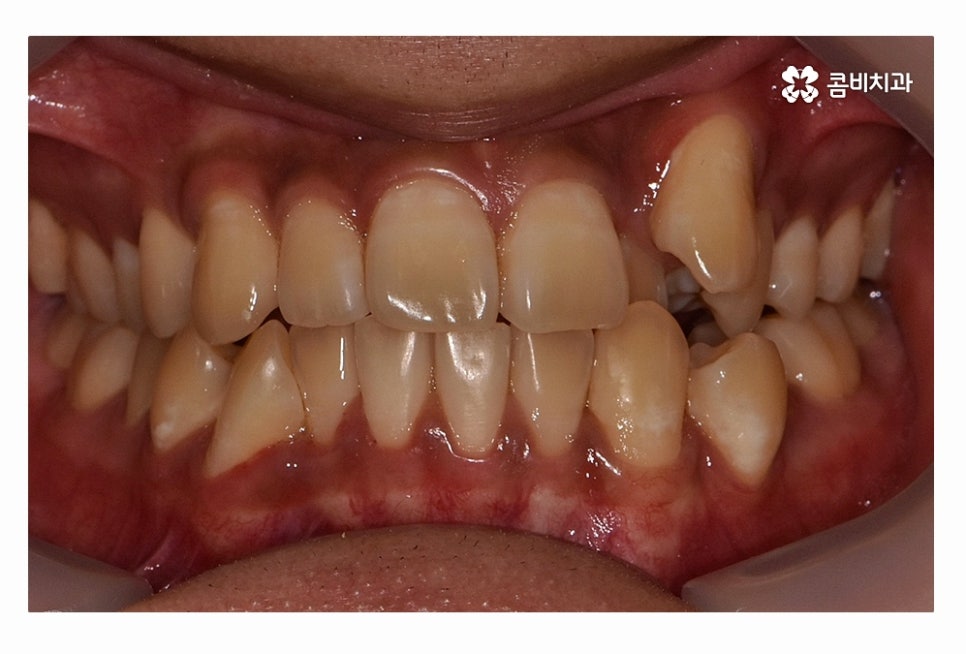

오늘 보시는 환자분의 사례처럼 덧니가 치아끼리 겹쳐 있는 경우에

치아의 이동 공간 확보를 위해서 덧니 발치 필요한 사례였으며

교합과 치아교정 후 얼굴 변화를 고려할 때도 치아교정 과정에서

발치가 필요한 사례였다고 볼 수 있어요.